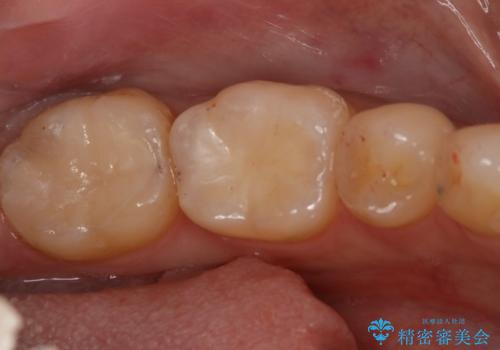

- 右下6番のメタルインレー脱離のため来院。

セラミックの治療を希望されたため切削量を考慮し、セラミックインレーでの治療を選択しました。

う蝕が深くまで進行していたので、CRで裏層した上で形成・印象をしています。